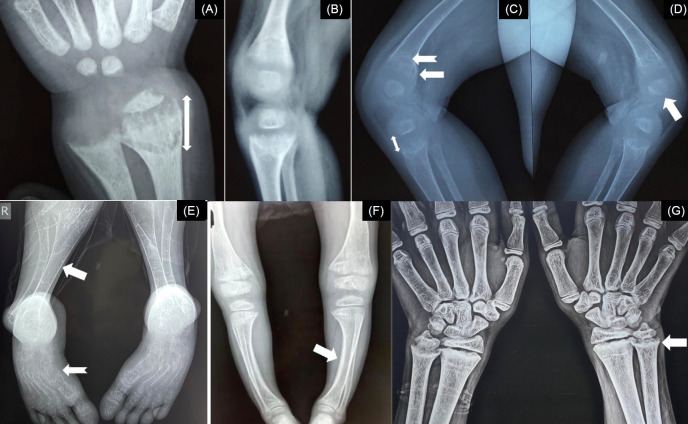

Rickets, one of the leading causes of bony deformities and short stature, can be calciopenic (inciting event is defective intestinal calcium absorption) or phosphopenic (inciting event is phosphaturia). Early diagnosis and timely treatment of rickets are crucial for correction of the limb deformities. Guidelines exist for nutritional rickets, but the diagnosis and management of the relatively uncommon forms of rickets are complex. This consensus aims to formulate a simplified diagnostic approach for rickets, especially in resource-limited settings. The consensus statement has been formulated by a 29-member committee from the Endocrine Society of Bengal. The process included forming a working group, conducting a literature review, identifying controversies, drafting, and discussion at a consensus meeting. Participants rated their agreement with the clinical practice points, and a 70% consensus was required. Input integration and further review led to the final consensus statements. Children with suspected rickets should initially be examined for distinctive skeletal deformities. The diagnosis of rickets should be confirmed with characteristic radiographic abnormalities. It is advisable to order tests for serum calcium, inorganic phosphorus (Pi), liver function, 25-hydroxyvitamin D (25OHD), parathyroid hormone, creatinine, and potassium in all patients with rickets. In cases of refractory rickets, it is also recommended that assessments be conducted for spot urine calcium, Pi, creatinine, and, blood gas analysis. In children with rickets and metabolic acidosis, tests for glycosuria, uricosuria, aminoaciduria, low molecular weight proteinuria, and albuminuria should be conducted. In children with resistant calciopenic rickets and sufficient serum 25OHD levels, serum 1,25(OH)2D concentration should be tested. 1,25(OH)2 D and fibroblast growth factor 23 estimation is useful for certain forms of phosphopenic rickets.